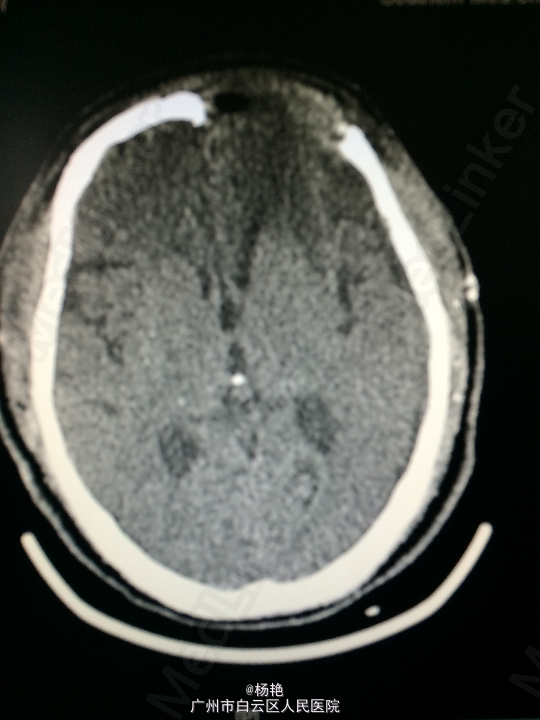

主诉:反复头痛2年加重1周 病史:患者诉两年前无明显诱因反复出现头晕头痛不适,近一周来症状加重,无恶心呕吐、无行走不稳、肢体乏力、意识障碍等。遂至当地医院诊治,行头颅CT、MR检查均提示颅内占位,良性可能性大,考虑脑膜瘤。今患者为求进一步治疗而入我院。

查体:神经系统查体未见明显异常 辅助检查:头颅MR提示:左侧额叶区域较大类圆形肿物,多考虑脑膜瘤可能;大脑前动脉及中动脉受压,中线偏移。

诊断:左额叶脑膜瘤 处理:在静脉全麻下行左侧额底脑膜瘤切除术,术后病理提示:脑膜瘤